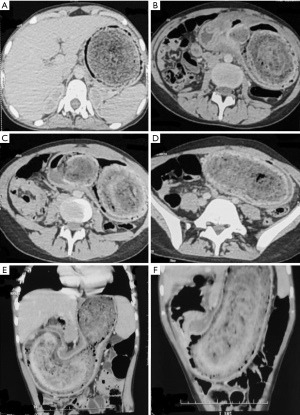

Once ingested, hair and fibers become trapped within the gastric folds, disrupting normal peristalsis. Lipid and mucus deposits contribute to the formation of a smooth, glistening mass, often causing halitosis. Gastric acid exposure denatures the hair, giving it a blackish color regardless of its original shade (12). Over time, the mass molds to the shape of the stomach (Figure 1) and may extend beyond the pylorus into the duodenum or small intestine (13), leading to Rapunzel syndrome, first described by Vaughan in 1968 (14). This can cause intestinal obstruction, intussusception, pancreatitis, or cholestatic jaundice due to ampullary obstruction. Detached fragments may migrate distally, resulting in small bowel obstruction.

However, computed tomography (CT) remains the gold standard for diagnosing trichobezoars (31). As first described by Newman in 1988 (44), the characteristic CT appearance is an intragastric mass made of compressed concentric rings with entrapped air and debris (46) (Figure 2). CT also helps determine the extension of the bezoar into the duodenum (Rapunzel syndrome), locate any detached fragments that may have migrated into the small intestine, and assess for complications such as reactive gastritis (manifested as wall thickening with mucosal enhancement), obstruction, perforation, or intussusception (47).